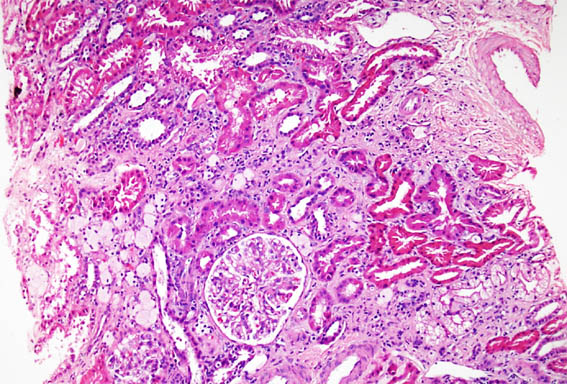

Figura 2. H&E, X200.